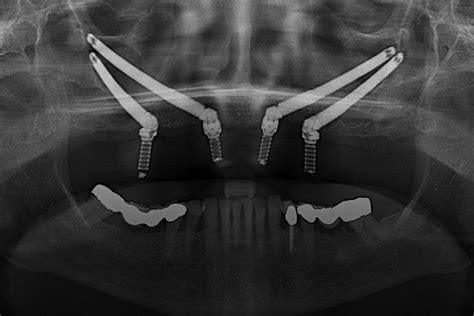

ANA MARÍA: Atrofia maxilar severa - Implantes cigomáticos y anteriores, regenereación ósea

Implantes Cigomáticos: Una Alternativa para Maxilares Atróficos

Los implantes del maxilar superior atrófico son cada vez más habituales para corregir diversos problemas. Por esta razón, hemos escrito uno de los manuales actuales más completos sobre una gran cantidad de técnicas realizadas. El formato está perfectamente orientado para que las específicas y completas explicaciones, junto a un extraordinario repertorio de imágenes de gran calidad, sean de gran ayuda tanto como para profesionales en formación como para especialistas que quieran mejorar sus prestaciones para dar el mejor servicio.